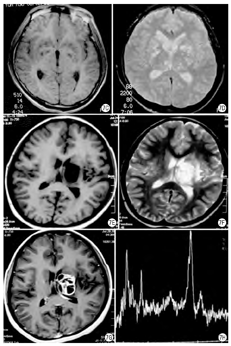

病理改变:HIV脑炎早期大脑形态无明显改变,以后出现不同程度的脑萎缩,多见局部萎缩表现,如额叶、颞叶比较明显,晚期可见脑室扩张,脑组织明显萎缩,重量减轻。HIV脑炎的病灶分布于大脑白质和灰质中,深部灰质(基底核、脑干核团)病变比较严重;也可见脑组织发生灶性或大片坏死。镜下检查,HIV脑炎以多核巨细胞形成于小胶质结节比较有一定特征性,故又有"多核巨细胞脑炎和结节性脑炎"之称。特征表现为广泛分布的小胶质结节浸润,即小胶质细胞增生,聚集成小结节。一般多核巨细胞和小胶质细胞结节可视为HIV脑炎的病理诊断依据(图2A、图2B)。

影像表现:MRI表现为弥漫性或局灶性脑白质异常,脑沟增宽,脑室扩大,脑总量减少,呈片状长T1长T2信号(图2C、图2D)。有研究显示,在MR DTI上,额叶、胼胝体、海马ADC值增高[3]。